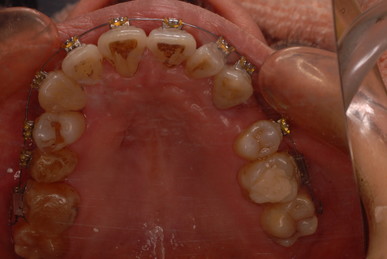

写真左の歯のうち過剰歯と糸きり歯の隣を抜きました。

矯正治療一ヶ月後です。歯並びのガタガタはすぐよくなっています。